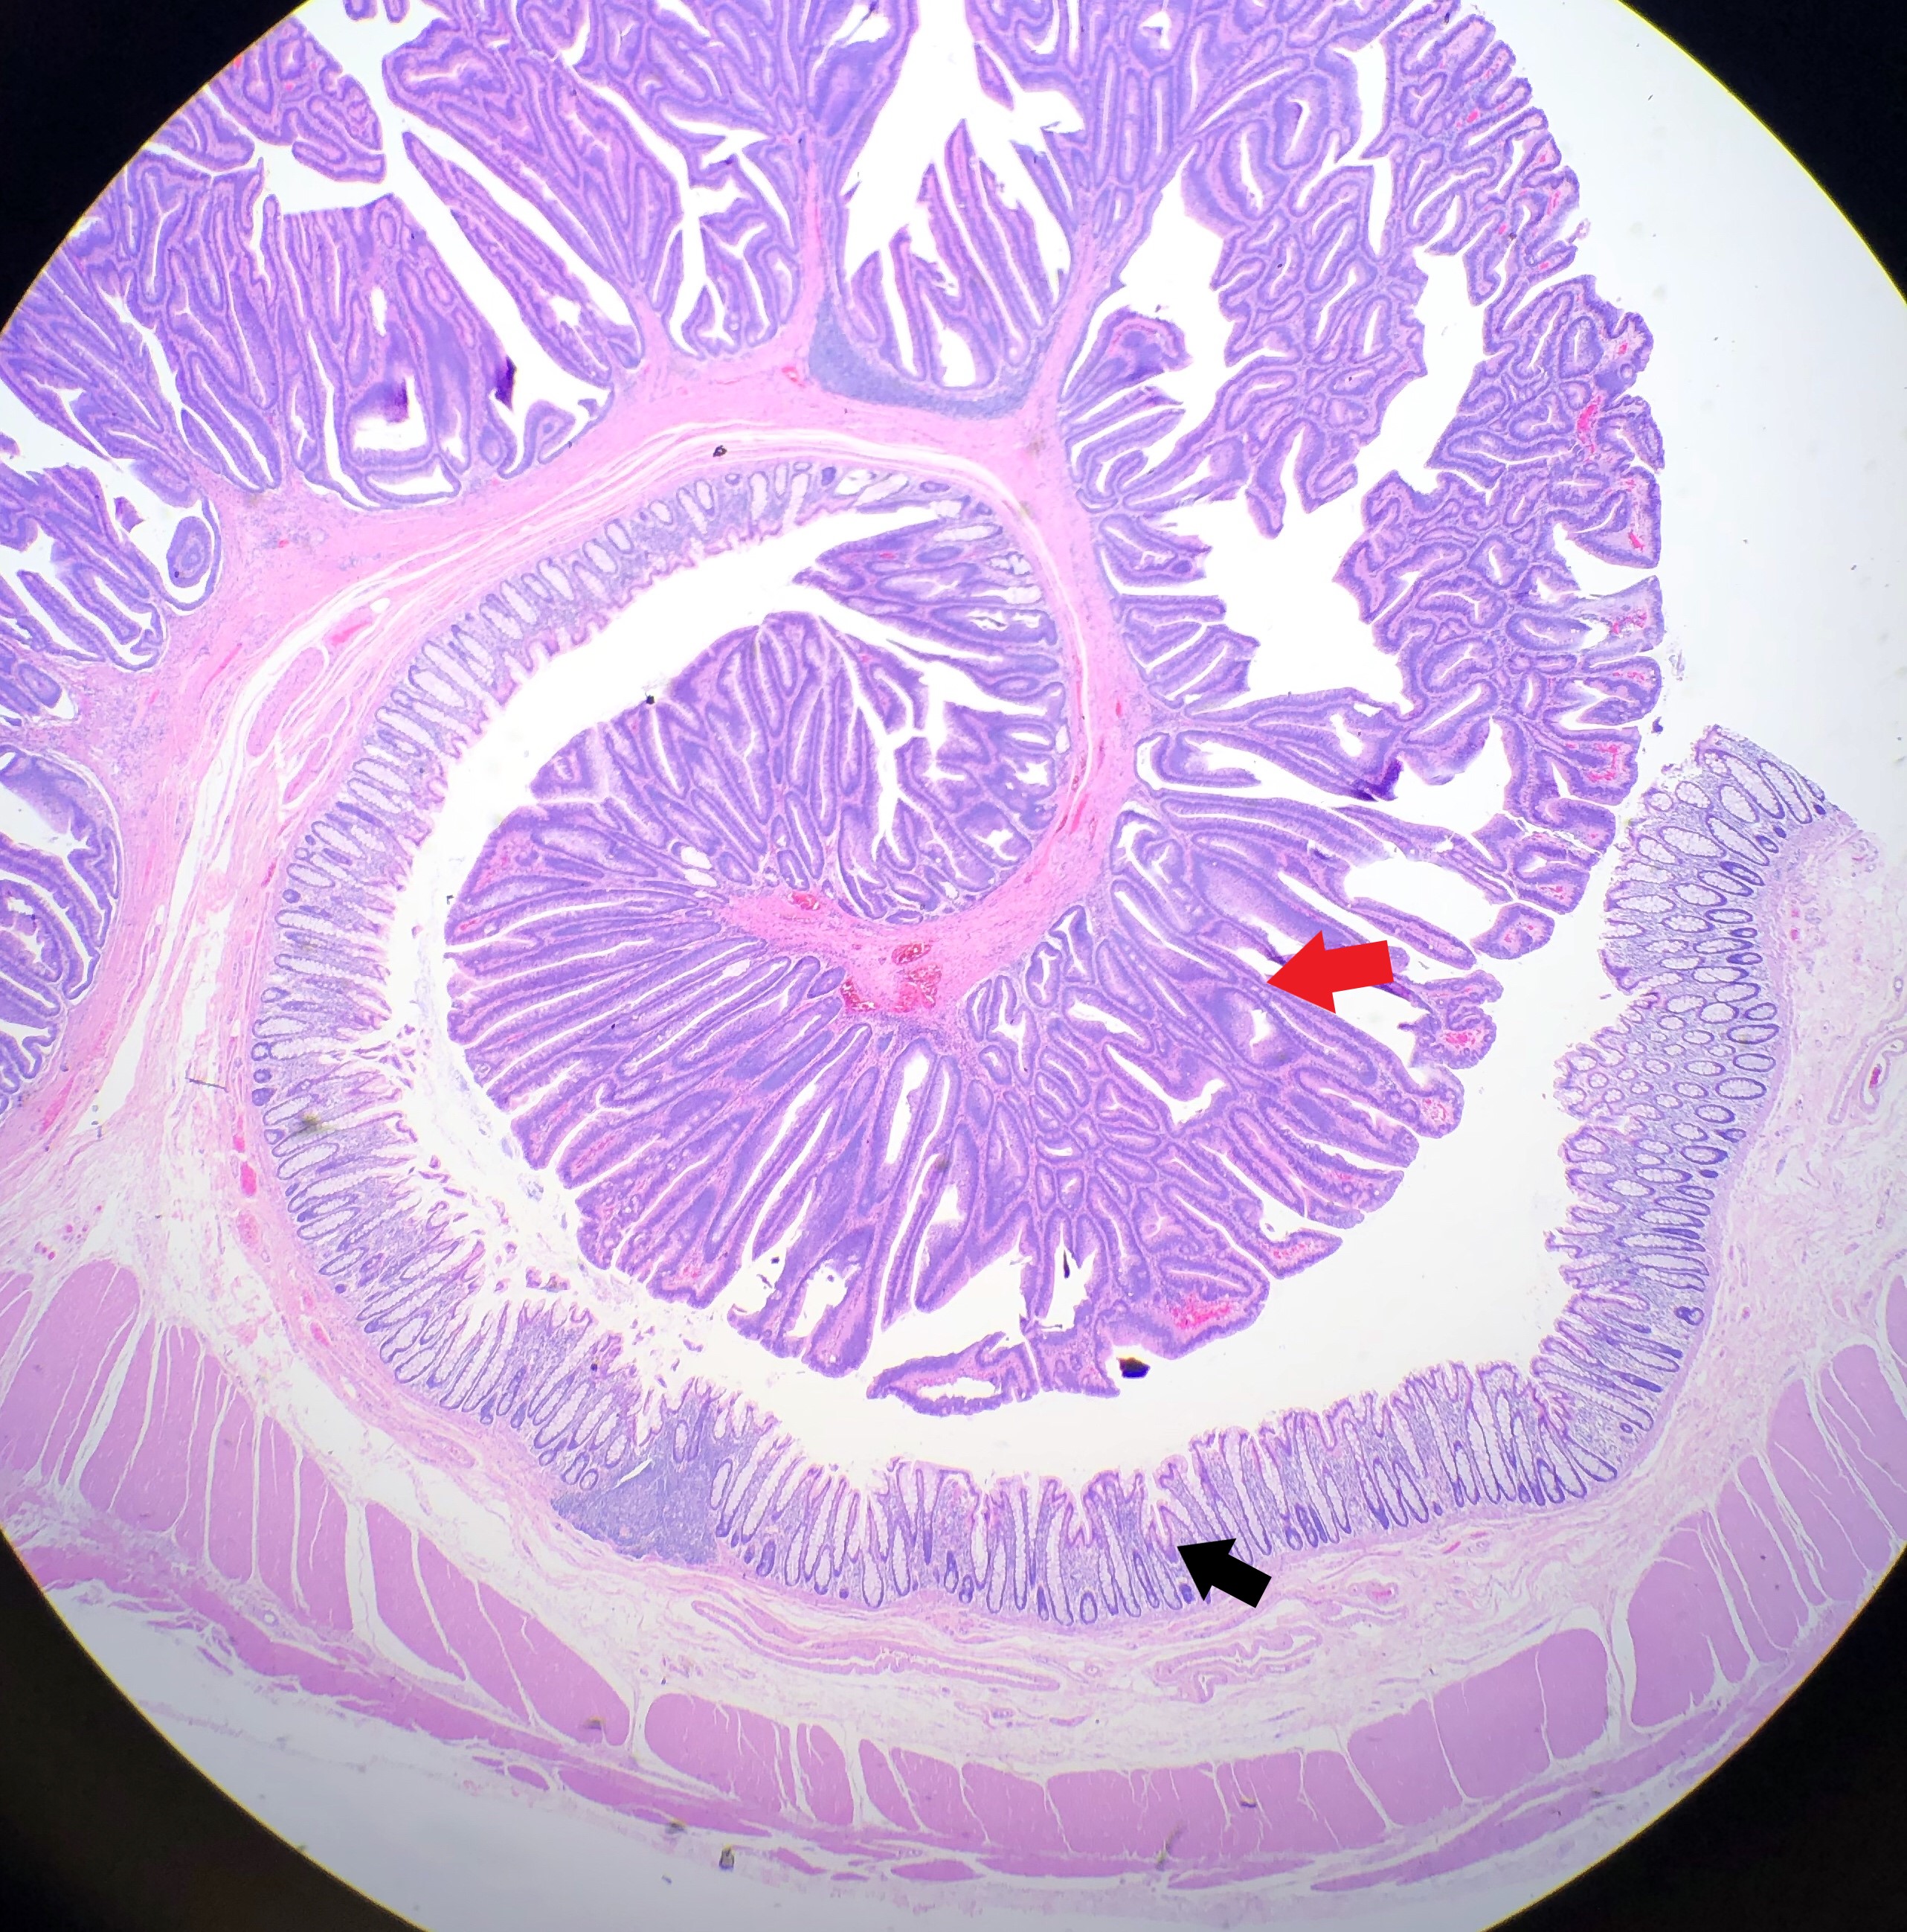

Essentially, this patient was found to have Li-Fraumeni after the second manifestation of an acute sarcoma—the first being osteosarcoma in her teenage years and the second breast cancer in her 30s. Both cancer diagnoses were treated accordingly, and this patient was going through routine work-up for anemia before being referred to the Mayo Clinic. By the time the patient reached there, the clinical investigation included a battery of testing for causes of anemia—all within normal limits—so a bone marrow examination was performed which revealed a significant, though not acute (<20% blasts), myelodysplastic process. A follow-up in-house bone marrow collection revealed hypercellular marrow, now in acute myeloid proliferation, with abnormal myeloid cell maturation and very complex cytogenetics. She had a very complex karyotype and several detectable mutations which were consistent with the WHO’s classification and description of therapy-related myeloid neoplasm as a sequale to the treatments she received for her prior cancers. In the setting of a patient with LFS, it is almost impossible to avoid malignancy. The following slides are a (very abridged) summary taken from my presentation of this patient’s case:

- Acute Myeloid Leukemia and Myeloid Sarcoma

In a recently published paper in Histopathology, I was part of a team at the UAB hospital’s department of pathology which discussed their experience with patients diagnosed with myeloid sarcomas (MS). The point was to look for correlations with MS to connect the entity with age, sex, location of tumor, AML status, genetics, etc. Ultimately, what became the highest predictor of disease was a complex karyotype, consistent with other concurrent literature. With respect to this patient, what if there was another soft tissue (or other location) sarcoma alongside her myelodysplastic picture. What if she had a low blast count, or hypocellular bone marrow, or necrosis/fibrosis, or had received G-CSF? Would AML with myeloid sarcoma be considered in this diagnostic setting, would myeloid sarcoma be something to worry about in her future or in her clinical history as a misdiagnosis? The take-home message would be to pay close attention to patient clinical history and stay both focused on the current diagnostic work-up but also open enough to avoid pitfalls in diagnostic challenges.